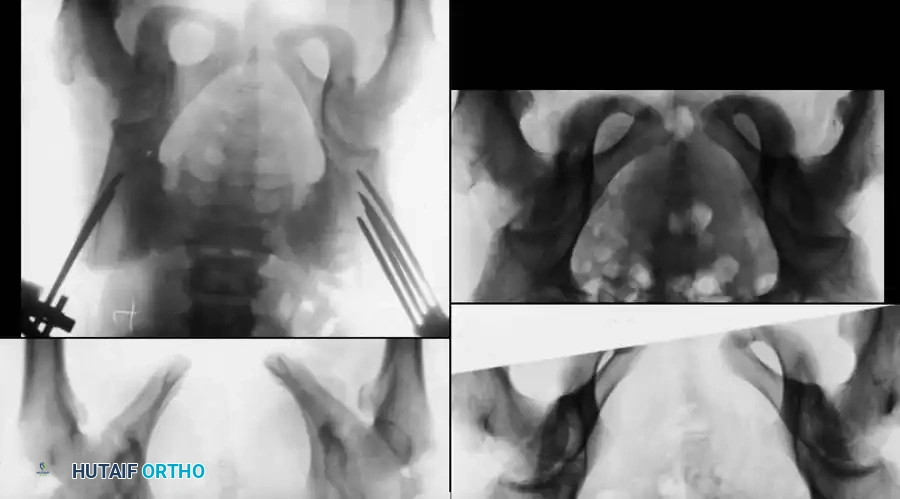

Operative Technique: Application of Pelvic External Fixator

External fixation is the workhorse for acute, hemodynamically unstable "open-book" (anteroposterior compression) fractures in children. It rapidly reduces pelvic volume, promoting tamponade of retroperitoneal venous bleeding.

Radiographic sequence demonstrating the application of a pelvic external fixator to close a severe diastasis of the symphysis pubis.

Step-by-Step Procedure:

1. Positioning: Supine on a radiolucent trauma table. Ensure the abdomen and pelvis are prepped widely to allow for concurrent laparotomy if required by general surgery.

2. Incision and Approach: Make a 1-2 cm incision over the anterior inferior iliac spine (AIIS) or the iliac crest, depending on the chosen pin trajectory. The supra-acetabular (AIIS) corridor is biomechanically superior and preferred in older children.

3. Pin Insertion (Supra-acetabular):

* Bluntly dissect down to the bone between the sartorius and rectus femoris.

* Under fluoroscopic guidance (Obturator Outlet and Iliac Inlet views), place a drill guide.

* Insert 4.5 mm or 5.0 mm Schanz pins (depending on patient size) directed from the AIIS toward the posterior superior iliac spine (PSIS), staying strictly within the dense bone corridor above the sciatic notch.

4. Frame Assembly: Connect the pins with a carbon fiber rod system.

5. Reduction: Apply internal rotation compression forces to the pins to close the symphyseal diastasis. Confirm reduction fluoroscopically.

6. Final Tightening: Lock the frame. Ensure the abdomen is not compressed by the bar to avoid abdominal compartment syndrome.